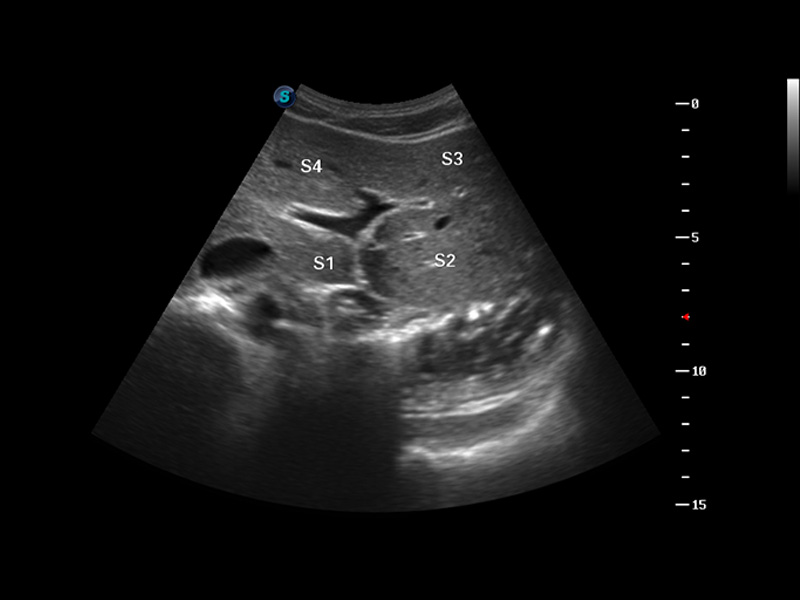

实时宽景成像

空间复合成像